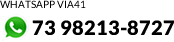

O Hospital Geral de Eunápolis (HGE) passou por uma expansão estratégica que amplia sua capacidade de atendimento e agiliza a condução clínica dos pacientes. Nesta quarta-feira (11), o prefeito Robério Oliveira entregou a nova sala do tomógrafo, a Enfermaria clínica cirúrgica e a sala de medicação, reforçando a estrutura da unidade e reorganizando os fluxos internos para atender de forma mais eficiente a população local e regional. Participaram do ato vereadores, a deputada estadual e primeira-dama Cláudia Oliveira, secretários, equipe administrativa da unidade hospitalar e servidores.

O tomógrafo, adquirido com investimento superior a R$ 3 milhões, viabilizado com o apoio do Governo do Estado da Bahia, foi instalado em ambiente próprio e tecnicamente adequado. O equipamento permite diagnósticos mais rápidos e precisos, fundamentais especialmente em casos de urgência e emergência.

O prefeito Robério Oliveira destacou que as ações representam um avanço estrutural permanente para o município. “Estamos fortalecendo o hospital e ampliando a capacidade do SAMU para oferecer respostas mais rápidas e seguras. Graças a Deus, contamos com o apoio e o empenho da deputada Cláudia Oliveira, que segue ao nosso lado nessa missão de reconstruir Eunápolis. Nosso compromisso é organizar uma rede de saúde eficiente, capaz de atender à população com mais qualidade e segurança”, afirmou.